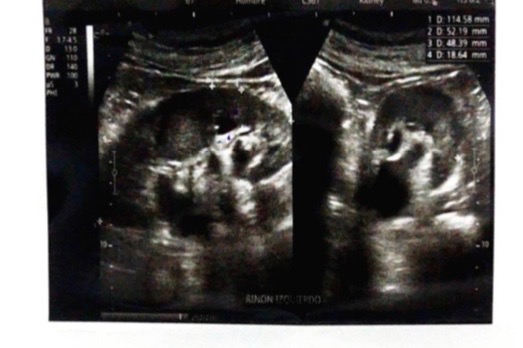

Uncle Tony lives in a Nicaragua that lacks modern medical care and his Diabetes was not properly managed. Sadly, his diabetes progressed to the point where his kidneys are severely compromised.

His doctor say that his kidneys are obstructed and the ONLY option is surgery. Otherwise, it's only a matter of time before his kidneys fail.